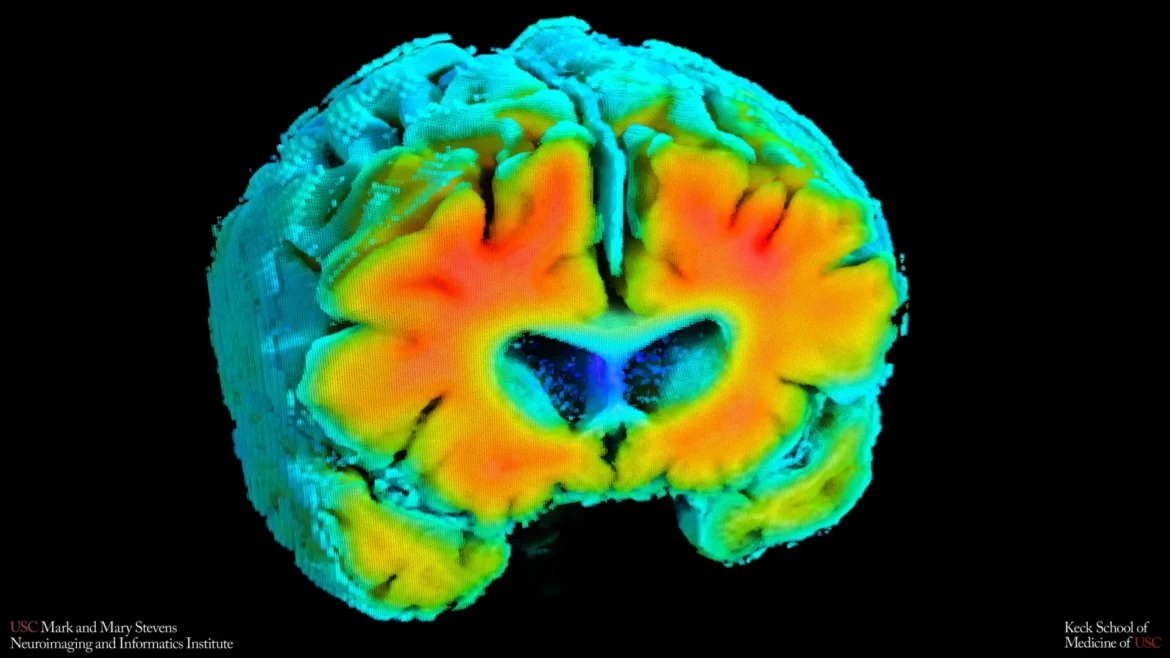

Small shifts in how blood moves through the brain and how brain cells receive oxygen may be closely connected to the risk of Alzheimer’s disease. That is the conclusion of new research from the Mark and Mary Stevens Neuroimaging and Informatics Institute (Stevens INI) at the Keck School of Medicine of USC.

The study, published in Alzheimer’s and Dementia: The Journal of the Alzheimer’s Association, examined older adults both with and without cognitive impairment. Researchers found that simple, noninvasive measures of brain blood flow and oxygen levels were linked to well known signs of Alzheimer’s, including amyloid plaque buildup and shrinkage of the hippocampus, the part of the brain that plays a central role in memory. The results suggest that the health of the brain’s blood vessels may influence the disease process early on and could help flag people at risk before noticeable symptoms develop.

“These vascular measures are capturing something meaningful about brain health,” said Meredith N. Braskie, PhD, senior author of the study and assistant professor of neurology at the Keck School of Medicine. “They appear to align with what we see on MRI and PET scans that are commonly used to study Alzheimer’s disease, providing important information about how vascular health and standard brain measures of Alzheimer’s disease risk may be related.”